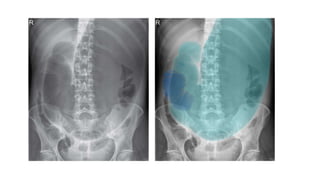

3) ABDOMINAL VISCERA 1

4) ABDOMINAL VISCERA 2